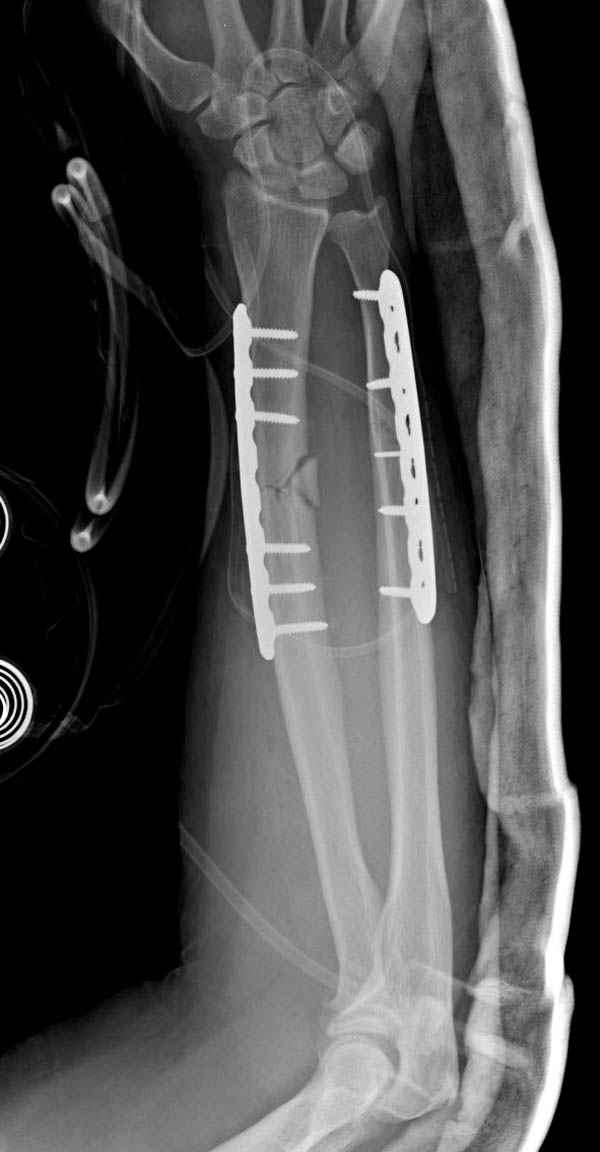

Наш недавний случай перкутанной фиксации "методом

Сиэтла" спицами 2.8 мм с резьбой на конце.

Прооперирован вчера на 13 день после поступления.

Больному 41 и из-за гемодинамической нестабильности в течение первых 7 дней был в реанимации под интубационной седацией.

Кроме перелома плеча у больного старый дистракционный перелом T12-L1 оперированный когда-то и кем-то, открытый перелом костей предплечья, который был прооперирован в ночь поступления, после I&D (хирургической обработки). Из-за разрыва селезенки при поступлении травма хирургами произведено удаление.